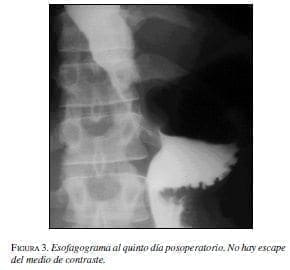

Con estos hallazgos el paciente fue llevado a cirugía; se realizó toracotomía lateral izquierda sobre el borde de la octava costilla y resección del divertículo usando TA 30 –3.5 mm (US Surgical). Luego se aproximaron los músculos sobre la línea de grapas. Seguidamente se practicó esofagomiotomía de aproximadamente 8 cm en la pared opuesta al divertículo por arriba y debajo del divertículo pero sin involucrar el EEI. Posoperatorio sin complicaciones y el paciente fue dado de alta al séptimo día. El esofagograma de control no evidenció escape del medio (figura 3). A los seis meses de la cirugía el paciente se encuentra asintomático y tolera dieta corriente; ha recuperado 7 kg de peso. La endoscopia de control fue normal, sin evidencia de reflujo.